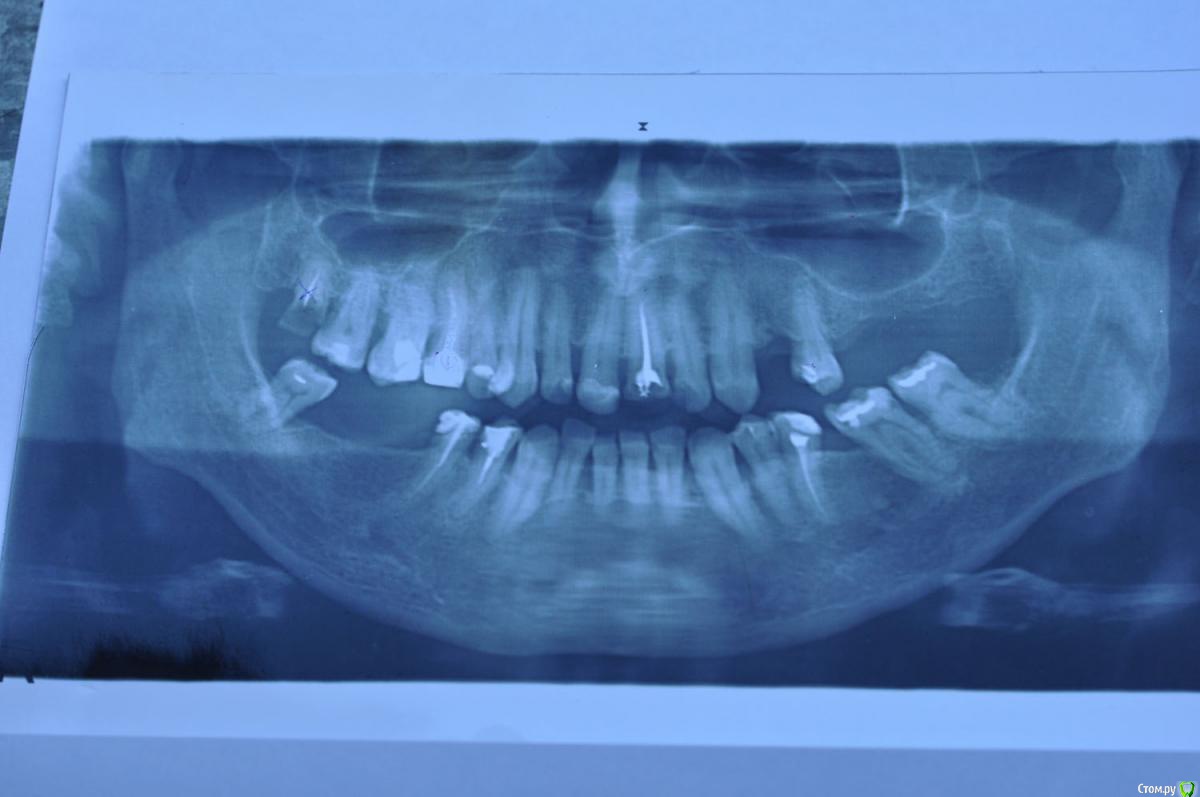

Родион Р. Опубликовано 14 июня, 2015 Поделиться Опубликовано 14 июня, 2015 Обращаюсь к профессионалам за помощью и советом. Был в 6-ти клиниках по поводу протезирования. В итоге растерялся среди многообразия вариантов плана лечения ( разброс цен от 35 до 200 т.р.). Нет ясности что делать с 1) 11 и 21 , 2) 16 и 15, 3) 23 и 25, 3) 48 и 45. Основной критерии а) необходимо и достаточно, б) надежность и функциональность, на последнем - красота. Убедительно прошу помощи по составлению профессионального плана. Заранее благодарю. Ссылка на комментарий

M@estro Опубликовано 14 июня, 2015 Поделиться Опубликовано 14 июня, 2015 1) перелечивание 16,1.5,2.1, 35,4.4,4.5.2) санация, удаление 1.83) установка имплантатов в области 2.4,2.6,2.7,4.6,4.7.+ синус-лифтинг4) покрытие депульпированных зубов одиночными коронками, изготолвеие коронок на имплантаты. 5) для эстетики - замена пломб во фронтальном отделе на непрямые реставрации. 2 Ссылка на комментарий

Vladimirov Опубликовано 14 июня, 2015 Поделиться Опубликовано 14 июня, 2015 1) перелечивание 16,1.5,2.1, 35,4.4,4.5. 2) санация, удаление 1.8 3) установка имплантатов в области 2.4,2.6,2.7,4.6,4.7.+ синус-лифтинг 4) покрытие депульпированных зубов одиночными коронками, изготолвеие коронок на имплантаты. 5) для эстетики - замена пломб во фронтальном отделе на непрямые реставрации. это уже от 200тр Ссылка на комментарий

Mailze Опубликовано 16 июня, 2015 Поделиться Опубликовано 16 июня, 2015 Спасибо за ответ! Вы правы, имея опыт с эндопротезированием сустава и не имея возможности приехать на лечение к Вам, я прошу Вас как профессионала альтернативный план лечения ( без имплантации). Чтобы взяв план за основу, как фундамент произвести лечение учитывая ньюансы которые можно определить только на очном приеме.( Вы даже не представляете себе, что в провинции нет узких специалистов, я не имею в виду стоматологию.) Заранее благодарю. Адаптировал план лечения профессионала M@estro под Ваши требования, только учтите, что этот план лечения не оптимальный, а компромиссный.1) удаление 1.82) перепломбировать корневые каналы 16, 1.5, 2.1, 3.5, 4.4, 4.5., санация,3) покрытие депульпированных зубов одиночными коронками,4) бюгельный протез с кламмерной фиксацией на верхнюю и нижнюю челюсть5) для эстетики - замена пломб во фронтальном отделе на непрямые реставрации. Ссылка на комментарий